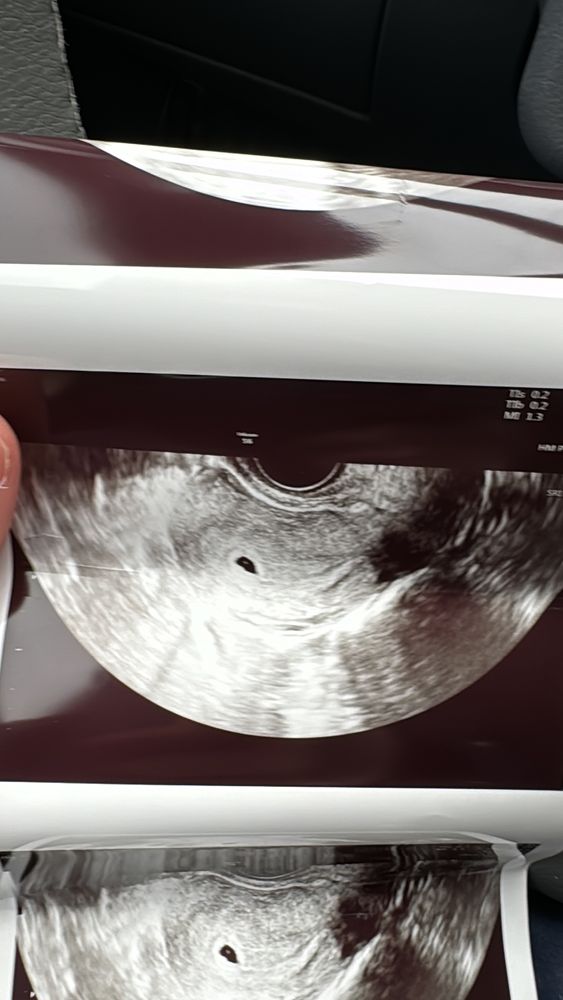

Анастасия , потопала,подтвердили маточную 😍 Изображение